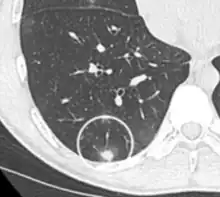

| Tomosynthesis of chronic fibrosing pulmonary aspergillosis | |

On chest X-ray and CT, pulmonary aspergillosis classically manifests as a halo sign, and later, an air crescent sign.[22] In hematologic patients with invasive aspergillosis, the galactomannan test can make the diagnosis in a noninvasive way. False-positive Aspergillus galactomannan tests have been found in patients on intravenous treatment with some antibiotics or fluids containing gluconate or citric acid such as some transfusion platelets, parenteral nutrition, or PlasmaLyte.[23][24]